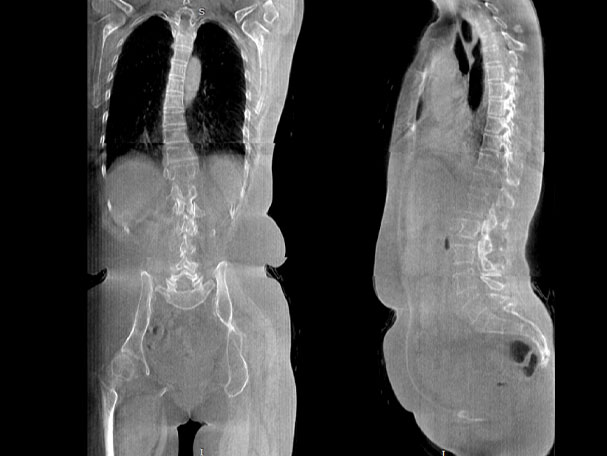

· 补位CT,提供负重位三维影像

· 引领普放走向三维精准诊断时代

填补常规CT/MR空白

腰椎